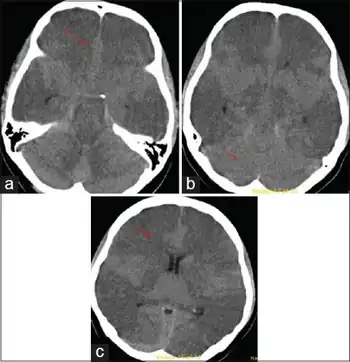

The regions of interest on SPECT brain imaging include a majority of all cortical regions, and the globus pallidus in Carbon monoxide poisoning. Based on medical literature on SPECT brain imaging, signature patterns for toxic encephalopathy is a nonspecific patchy, diffuse pattern on the cortex, and sometimes is shown in subcortical regions, if exposure was severe.

Rapid diagnosis is important to attempt to prevent further damage to the brain and further neurologic deficits. It is a diagnosis of exclusion, so a full work up for other possible etiologies (hepatic, uremic, infectious, oncologic) should be performed. In addition to the neurological examination, diagnostic testing could include MRI, PET or SPECT brain imaging, EEG, QEEG and most importantly, neuropsychological testing. Screening for heavy metals, as well as other toxins, should be done immediately as those are some of the most common causes and the patient can then remove themselves from the dangerous environment. In addition, a full examination of blood (CBC) and metabolites (CMP) should be done.